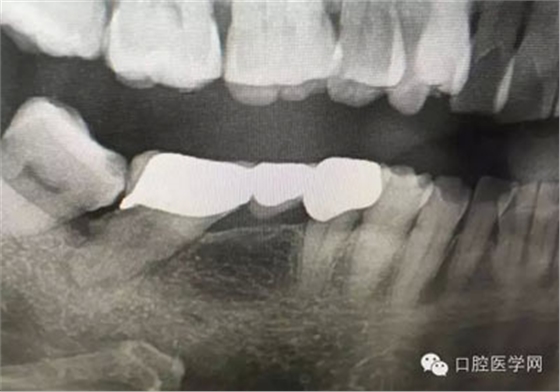

根管再治療是我們比較頭疼的,尤其是那些冠修復(fù)過的,我們有很多的麻煩需要去溝通,比如可能導(dǎo)致的側(cè)穿、可能沒有看到的腐質(zhì)、可能導(dǎo)致的崩瓷,或者是后期可能出現(xiàn)冠折......這些需要我們和患者好好的溝通。全瓷冠還好些,金屬冠根測(cè)的時(shí)候很是麻煩,總之我們做修復(fù)的時(shí)候不要單純的追求速度,追求效益,適當(dāng)?shù)淖⒁庀挛覀兊幕A(chǔ)治療和設(shè)計(jì)。

這是一例外院樹脂修復(fù)后十個(gè)月出現(xiàn)牙髓炎癥狀的患者。遇到這樣子的患者大家會(huì)怎么做,證明選擇,還有就是可做可不做治療的如何去平衡。